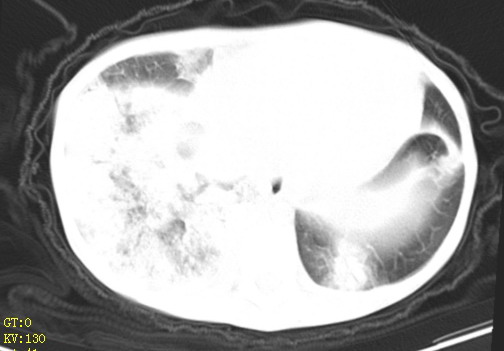

女,12岁,气促、咳嗽2天,3个月前查胸片示:两肺感染,急诊入院查ct,血常规等未检查。

双肺中下野不规则片絮状阴影,中外带明显,双侧胸腔少量积液,心影增大,心腔密度减低,隆突下及左侧气管旁见钙化淋巴结影,考虑双肺感染、心衰;建议结合临床除外h1n1并急性心衰,先心不能排除。

两肺多发片絮状模糊影,以下肺外带居多,内见支气管气像,纵膈窗未减影,两侧胸腔积液,心影增大,结合心超,支持重症肺炎,非常时期,甲型h1n1流感不排除。